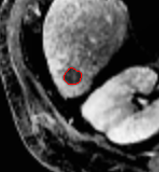

(1) Brain MR (2) Liver MR (3) Liver CT (4) Lung CT

We first introduce a method for connecting the output of a CNN to an ACM, yielding a model for the precise delineation of lesions, to which we refer as Deep Active Lesion Segmentation (DALS) (Figure 4). We then go further to introduce a truly unified framework (Figure 5) that bridges the gap between ACMs and CNNs by leveraging a novel, automatically differentiable level-set ACM with trainable parameters that allows for back-propagation of gradients and can be end-to-end trained along with a backbone CNN from scratch, without any CNN pre-training. The ACM is initialized directly by the CNN and utilizes an energy functional that is locally-tunable by the backbone CNN, through 2D feature maps. Thus, our work overcomes the big hurdle of fully automating the powerful ACM approach to image segmentation. We have applied our proposed framework to the task of building segmentation in aerial images (Figure 6).

Deep Active Lesion Segmentation

[45]: Lesion segmentation is an important problem in computer-assisted diagnosis that remains challenging due to the prevalence of low contrast, irregular boundaries that are unamenable to shape priors. We introduce Deep Active Lesion Segmentation (DALS), a fully automated segmentation framework that leverages the powerful nonlinear feature extraction abilities of FCNs and the precise boundary delineation abilities of ACMs. Our DALS framework benefits from an improved level-set ACM formulation with a per-pixel-parameterized energy functional and a novel multiscale encoder-decoder CNN that learns an initialization probability map along with parameter maps for the ACM. We evaluate our lesion segmentation model on a new Multiorgan Lesion Segmentation (MLS) dataset that contains images of various organs, including brain, liver, and lung, across different imaging modalities—MR and CT. Our results demonstrate favorable performance compared to competing methods, especially for small training datasets. -